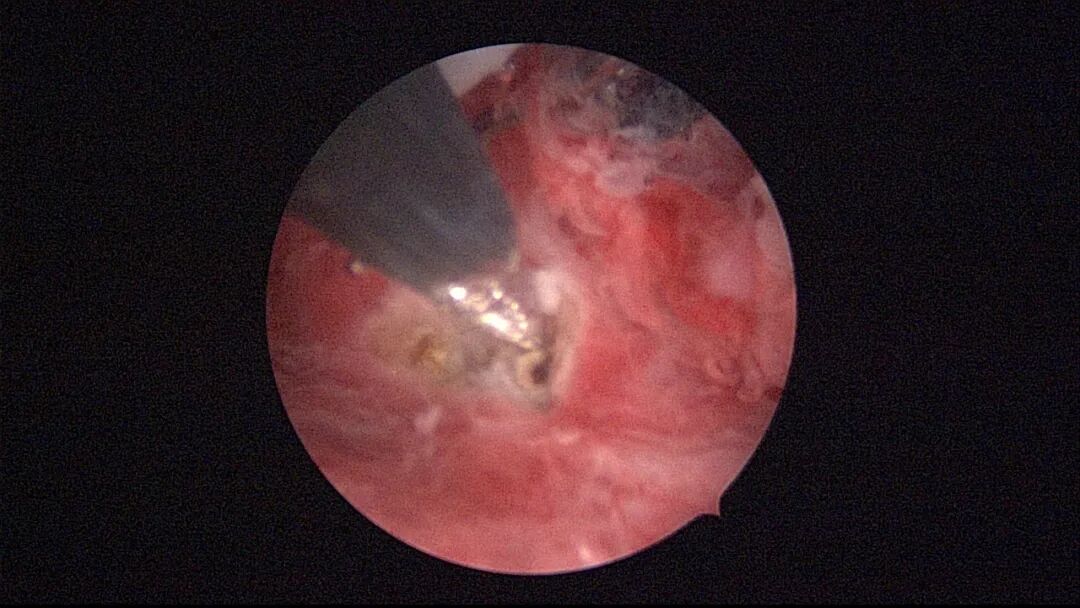

子宫腺肌症内膜息肉切除后丝线挂钩固定曼月乐并电凝图片及视频

操作步骤描述:宫腔检查镜可完成操作,扩张宫颈至7号扩宫棒,检查镜能轻松通过,避免镜鞘与节育环纵臂在宫颈管形成卡压及筷子效应,影响操作,或卡压摩擦阻力大带出节育环。可用单级电针在宫底扎出小凹坑做标记或作为置入挂钩的隧道(不是必须的)。将挂钩用异物钳直视下送入宫腔,或用中弯钳盲视下送入宫腔,异物钳夹持挂钩将倒钩端插入宫底肌层,越过倒钩。用环尾丝或不可吸收线在节育环顶端打结,形成一个线圈,直径约0.5cm~1cm,结打在线圈旁边,便于夹持操作。将环装回推杆送入宫腔,再夹住节育环固定线圈抵紧宫壁稍旋转就可以将线圈滑进挂钩缺口,挂到挂钩上,可再次向宫底推送挂钩少许,不必夹闭挂钩缺口,重力作用和内膜生长都会阻止线圈脱出,可以用电针电凝挂钩周围组织,进一步防止挂钩脱落。异物钳原位固定节育环,退出宫腔镜,距宫颈外口0.5cm~1cm剪断剩余尾丝。宫颈扩张到9号扩宫棒,冷刀系统异物钳夹持挂钩及线圈也可完成以上操作。

挂钩固定注意事项:月经干净3~7天手术,此时内膜最薄,利于挂钩固定到子宫肌层,如果内膜较厚,最好用负压吸引器去除内膜,暴露基底层,挂钩才能放置到位,也避免内膜掀起、出血等影响操作。挂钩尖端能轻松在子宫壁上粘附,然后调整钳的位置,将挂钩插入到宫底肌层。也可以在体外连接好挂钩和节育环,同时送入宫腔,异物钳在宫腔夹持挂钩并插入宫底肌层。术后复查B超节育环距宫底距离可能较大,个别达3cm左右,跟子宫大、宫壁厚、外加挂钩长度及线圈长度之和较大有关,保持这个距离不再延长即为手术成功。